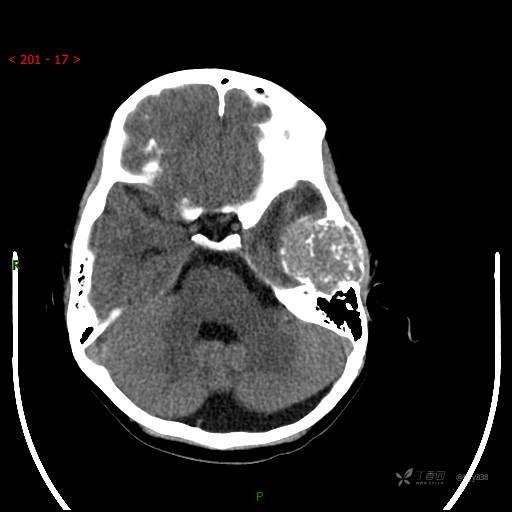

“典藏”病例分享。10岁儿童,头痛头晕一周余,CT、MRI 都有---结果公布~

简要病史:患者于一周前无明显诱因开始出现头痛头晕,无恶心呕吐,无肢体抽搐,无寒颤高热,无腹胀腹泻,无视力下降及视野缺损,上述症状休息后可稍缓解,未引起重视。 2天前患者头痛头晕不适加重,伴有恶心感,无呕吐,遂到当地人民医院行头颅CT检查示:左侧颞部占位性病变,今日家属为求进一步治疗,来我院门诊求治。门诊拟“左侧颞部占位性病变”收入我科。 患病以来,患者精神、饮食、睡眠尚欠佳,大小便如常,体力体重无明显变化。

临床诊断:左侧颞部占位

颅脑CT扫描